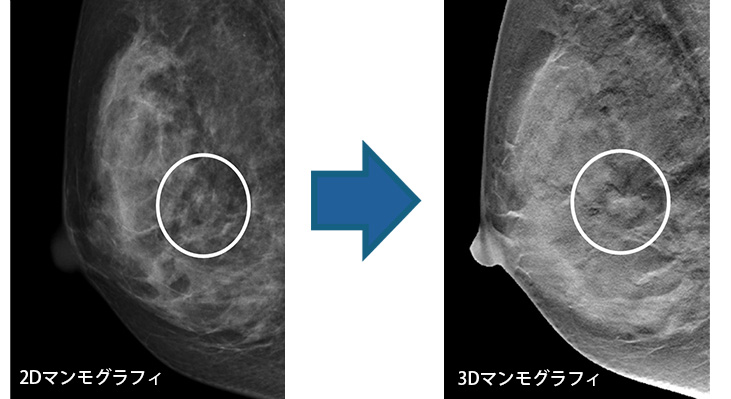

3Dマンモグラフィ(トモシンセシス)

新しい機能である乳房トモシンセシスが搭載されています。

従来のマンモグラフィではできなかった多方向からの撮影が可能となりました。乳腺内に隠れて見えなかった病変が確認できるようになります。